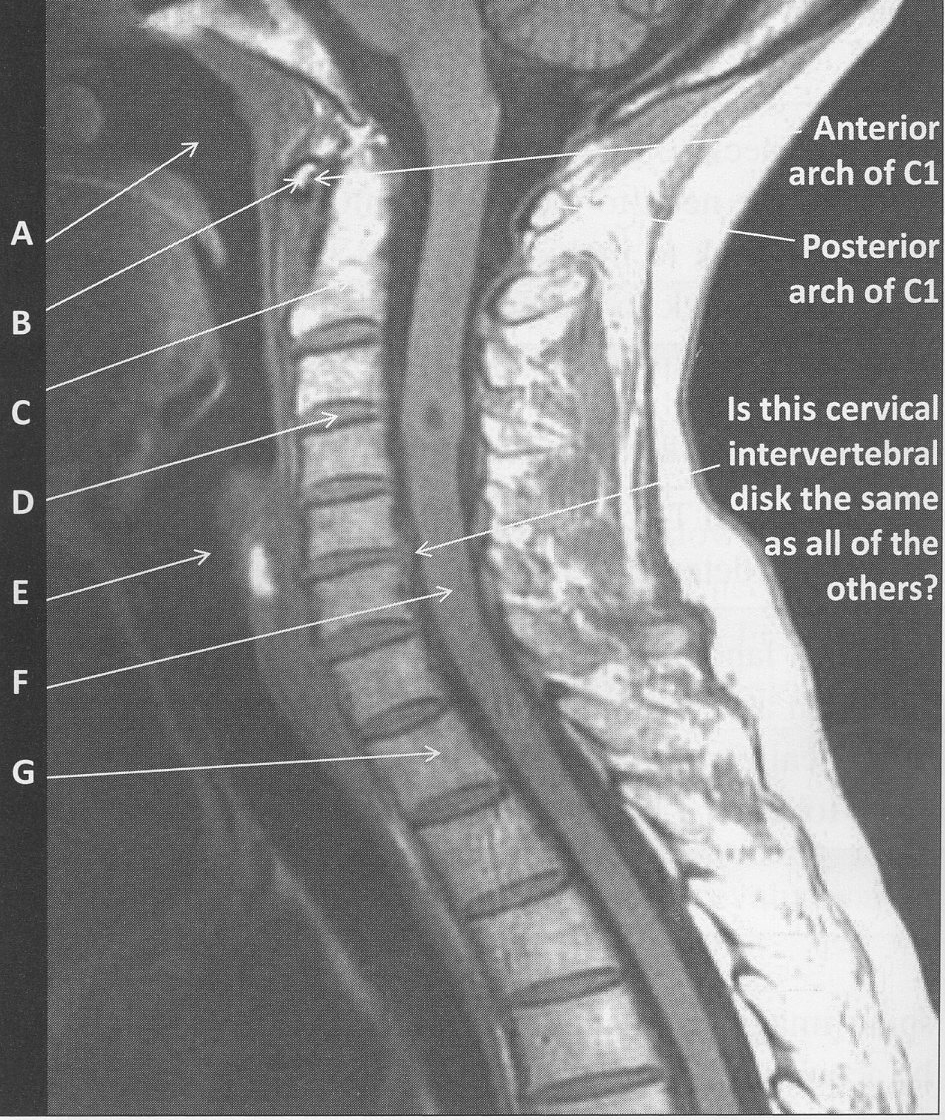

figure B 10 was acquiredin the _____plane

sagittal

figure B 10 is an example of a _____(weighting)

T1

figure B 10 arrow A

oropharynx

figure B 10 arrow B

anterior arch of C1

figure B 10 arrow C

Dens

figure B 10 arrow D

cervical disk

figure B 10 arrow E

trachea

figure B 10 arrow F

spinal cord

figure B 10 arrow G

vertebral body

figure B 10 the vertebral bodies of the C spine can be visualized because

hydrogen in cortical bone is too tightly bound to be “excited” by the MR process therefore cortical bone appears dark on MR images and outlines the vertebral body

bone marrow contains fat and water and therefore appears bright depending upon the scan parameters used to create the image

figure B 10 there is a slight cervical disk herniation at the level of

C5/C6